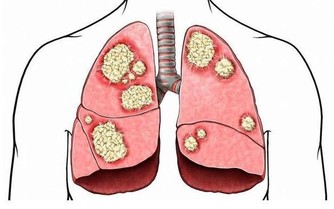

①不要抽煙。長期抽煙會導致肺癌、口腔癌、喉癌、食管癌等,同時還會增加患胃癌、肝癌等癌症的風險。

②經常吃魚。魚肉中多含不飽和脂肪酸,可以抑制腫瘤在身上出現的時間,還可以減緩腫瘤的生長,降低腫瘤的發生機率和轉移風險。